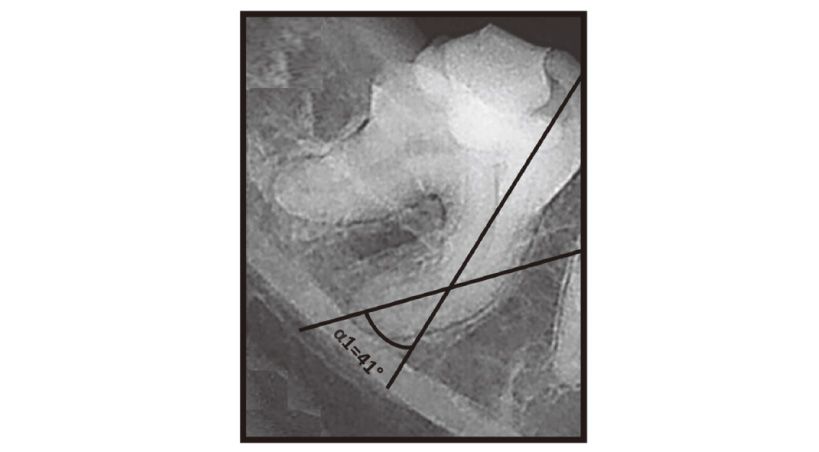

Retratamiento y restauración estética de incisivo superior con conducto radicular calcificado mediante un sistema de navegación dinámica

Reporte de un caso